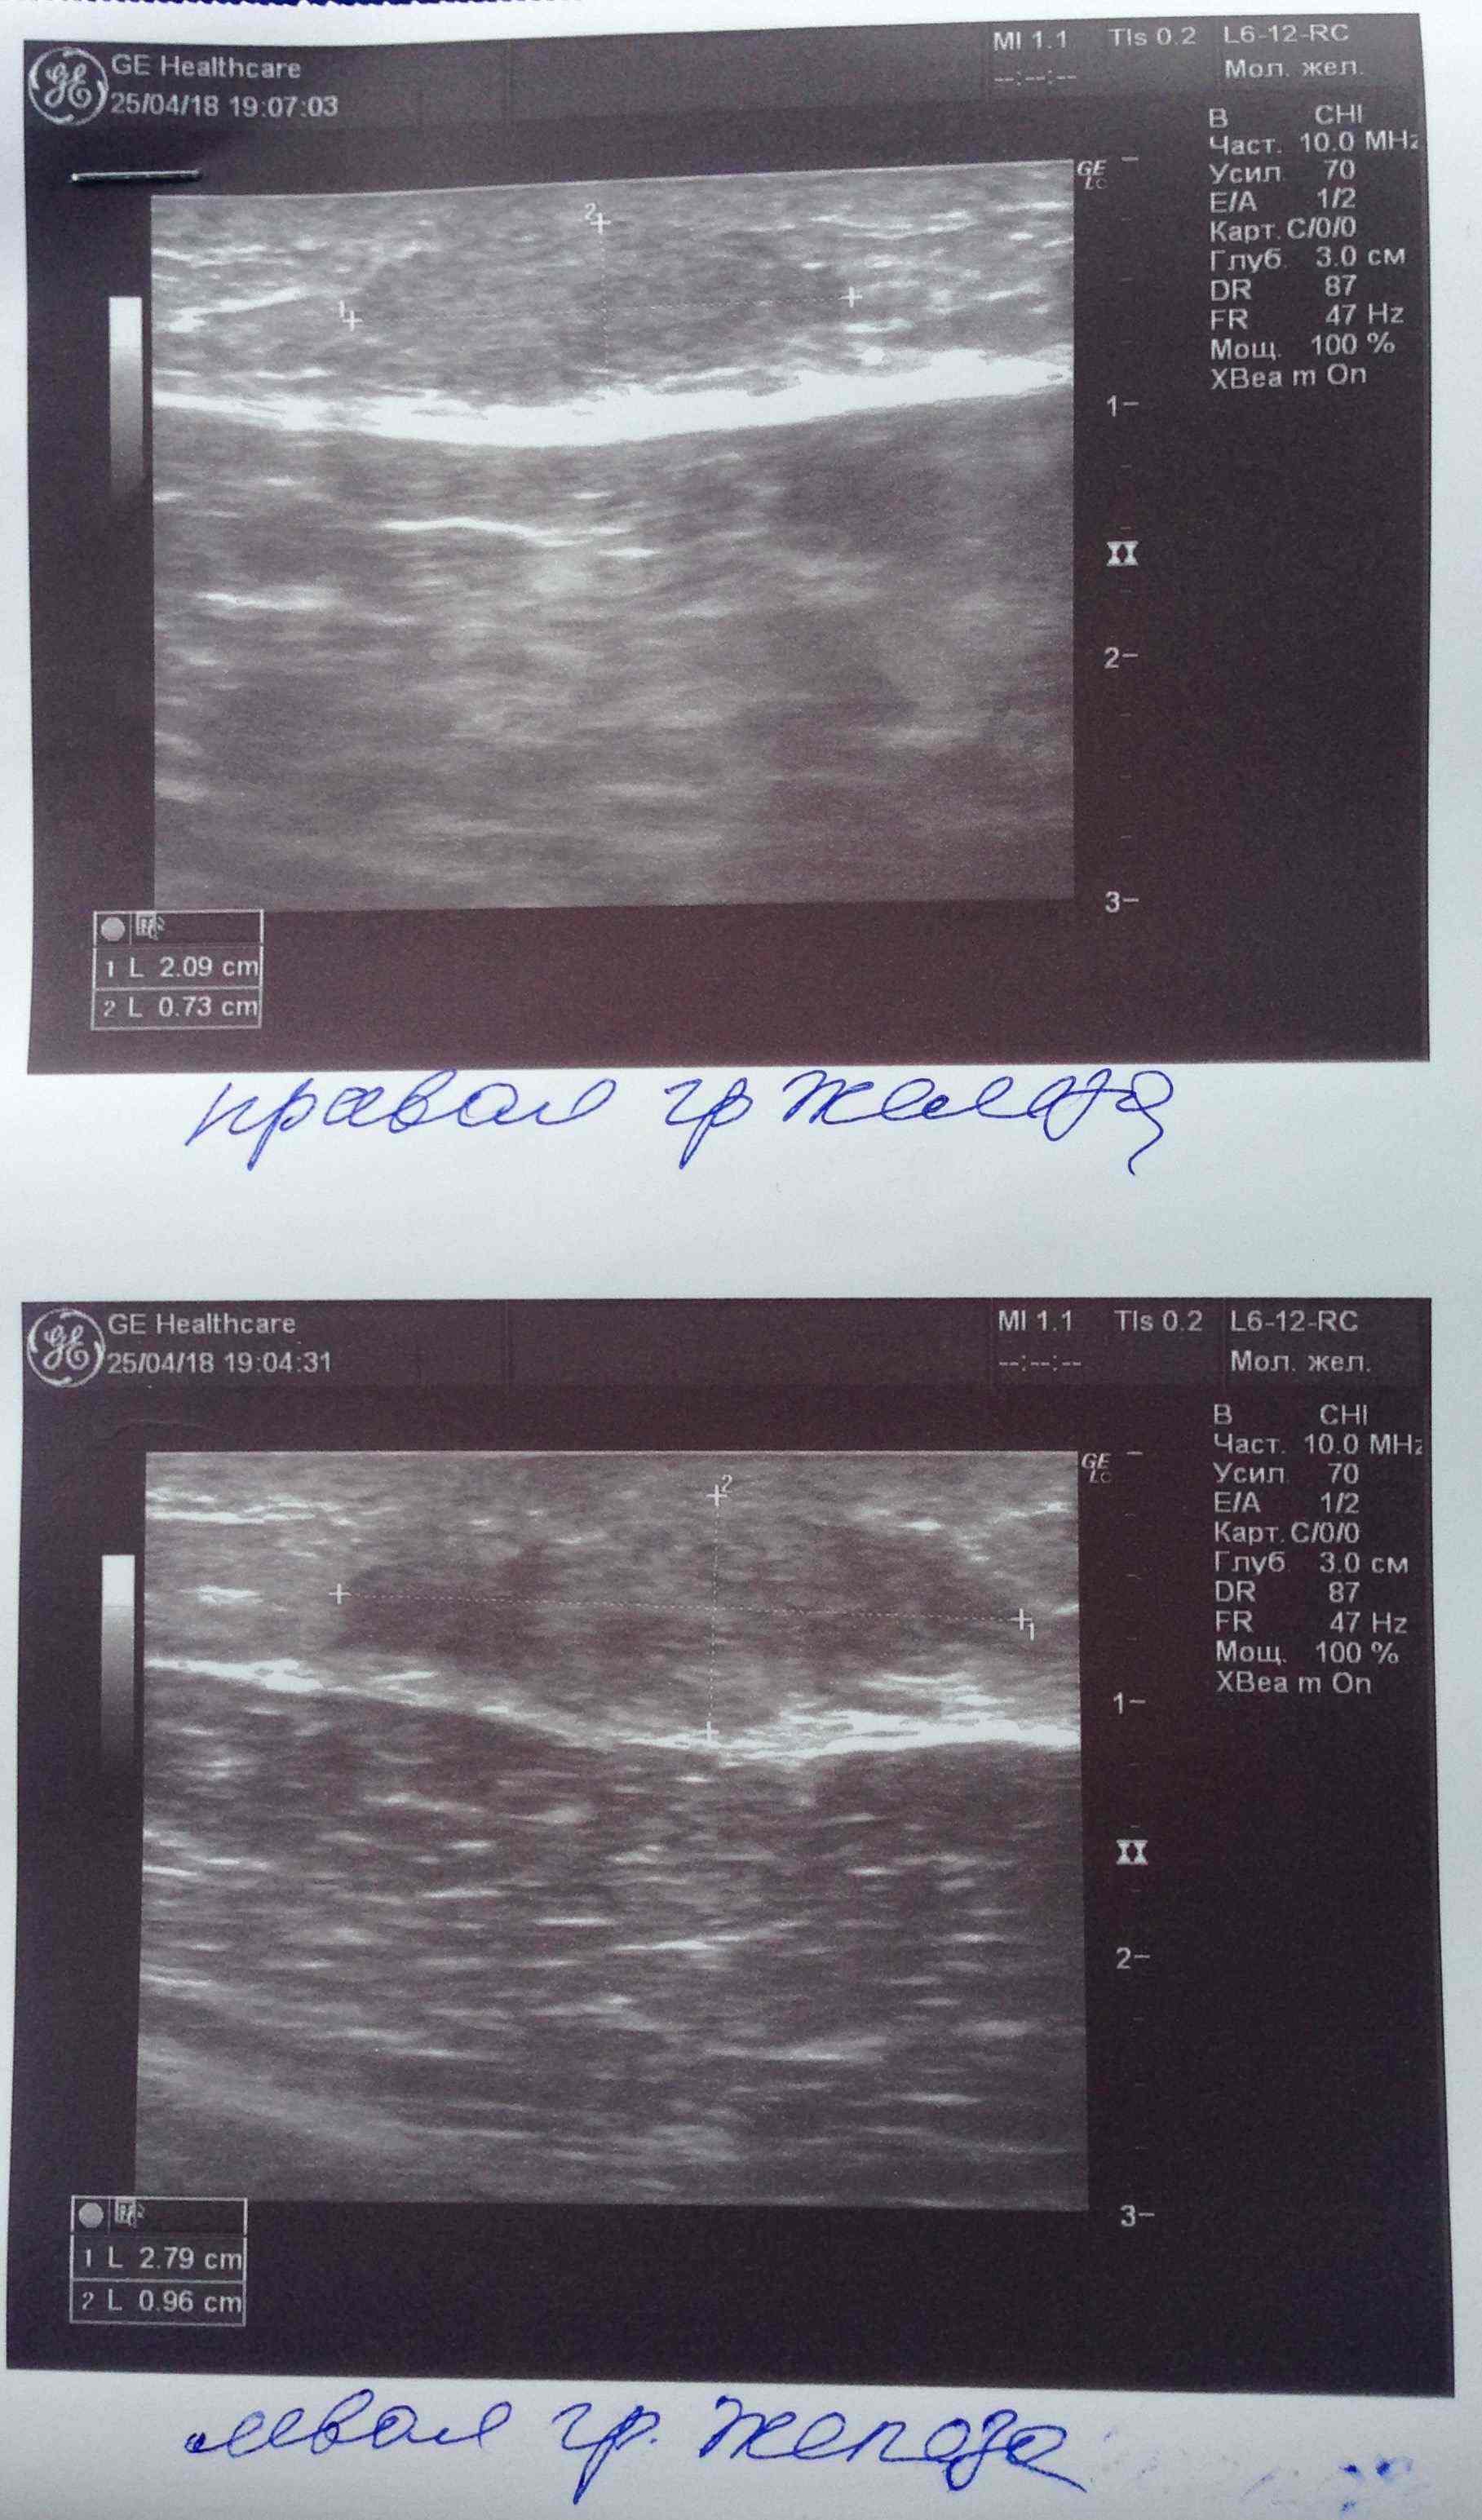

Парни всем доброго вечера! Недавно поднимали вопрос об уплотнении в области сосков на курсах с декой. Суть вопроса что анализы постоянно контролирую как строгая мамка бережет девственность дочки старшеклассницы и они находятся в референсах а уплотнение есть и как будто бы немного растет. Сгонял на УЗИ чтобы расставить все на свои места. В моем случае оно меня порадовало. Думаю что это не единичный случай поэтому и выкладываю инфу сюда. В моем случае гино и не пахло. Имеется небольшое уплотнение состоящее из фиброзно-жировой ткани. Всем здоровья и удачи:swag:

IMG_1400.JPG

Всем привет. Был курс нанфинил100+проп100. Набухли сиськи. Е2 и пролоктин в норме. PartyKill посоветовал сделать УЗИ .Результат: Эхо-признаки двусторонней геникомастии. Ну врачи привыкли всё драматизировать и слегка преувеличивать. Но лечиться всё равно надо. Посоветуйте братья . До этого проблем с гино небыло.Может эта реакция на нанфинил такая? (Юзал первый раз)Хотя дека прошлым курсом нормально так вкатила.Стаж 4 года, ну разумеется с отдыхом , ПКТ, сдачей анализов. Всё по фэн-шую, всё как мы любим.Сейчас идёт мост , энка250 . Хотелось бы подлечиться а с июня снова в бой )) Выручайте

Посмотреть вложение 14714 Всем привет. Был курс нанфинил100+проп100. Набухли сиськи. Е2 и пролоктин в норме. PartyKill посоветовал сделать УЗИ .Результат: Эхо-признаки двусторонней геникомастии. Ну врачи привыкли всё драматизировать и слегка преувеличивать. Ну лечиться всё равно надо. Посоветуйте братья . До этого проблем с гино небыло.Может эта реакция на нанфинил такая? (Юзал первый раз)Хотя дека прошлым курсом нормально так вкатила.Стаж 4 года, ну разумеется с отдыхом , ПКТ, сдачей анализов. Всё по фэн-шую, всё как мы любим.Сейчас идёт мост , энка250 . Хотелось бы подлечиться а с июня снова в бой )) Выручайте

Ну да, железа увеличина.

Давай тогда сделаем как советовал Дон, фарестон по 60 в день на месяц, после месяца сделать УЗИ повторно и посмотреть на динамику